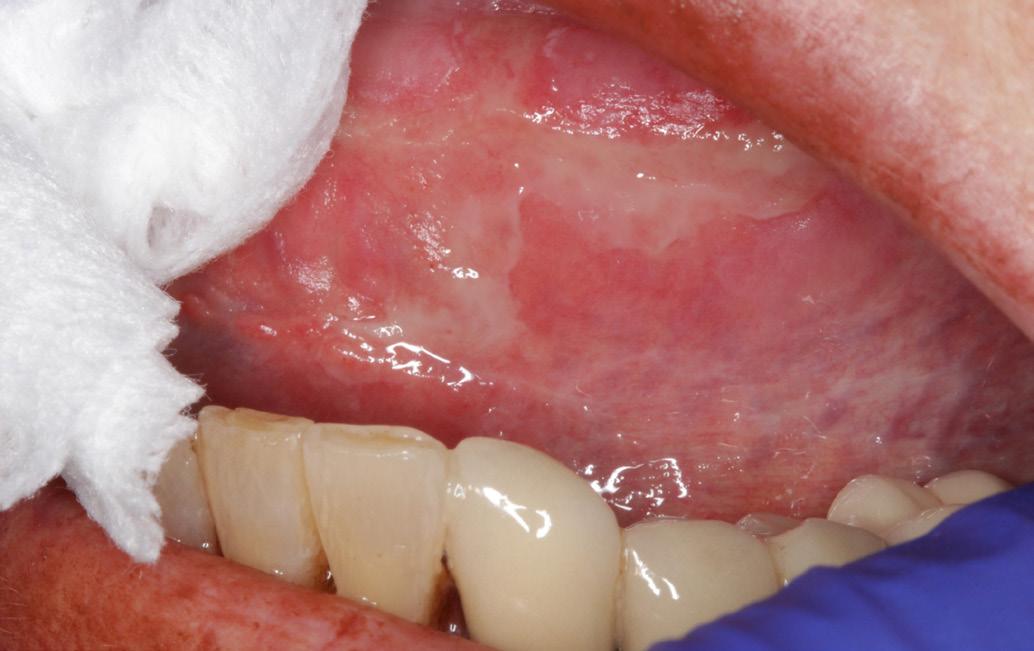

Oral examination revealed several shallow ulcers with erythematous borders affecting the buccal mucosa and the lateral borders of the tongue (Fig. 1). The patient reported significant discomfort while eating and speaking. Blood investigations were unremarkable. He was prescribed dexamethasone mouthwash and Difflam rinse, but there was no improvement. Methotrexate-induced oral ulceration was suspected. The patient’s rheumatologist was contacted, and methotrexate was temporarily withheld. Supportive therapy

with a topical corticosteroid mouth rinse was continued. Within two weeks, the ulcers healed completely (Fig 2). Methotrexate was later resumed at the same dose with continued 5 mg folic acid daily, and no recurrence was noted at follow-up.

Case 1

Fig. 1

Multiple painful ulcers on the buccal mucosa and lateral border of the tongue in a patient taking low-dose methotrexate.

Fig. 2 A

Multiple painful ulcers on the tongue and buccal mucosa in an 80-year-old female taking methotrexate and folic acid, resistant to initial topical therapy and antifungal treatment.